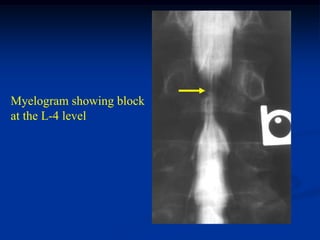

Case #1102

Axial and coronal CT scan

37 year male with chordoma in body of L-4

CT scan myelogram with block at L-4

Myelogram showing block

at the L-4 level